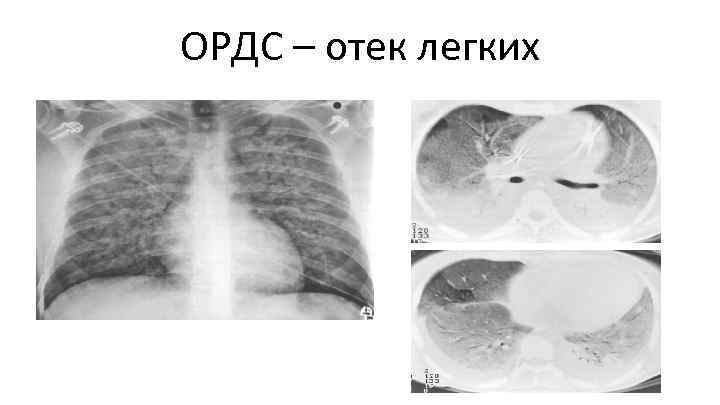

ОРДС: 1 -я неделя • Двухсторонние фрагментарные участки уплотнения (матовое стекло/консолидация) – Симптом «лоскутного одеяла» • • • Распределение более кортикальное Гравитационный (передне-задний) градиент Уменьшение объема легких Воздушная бронхография Небольшой плевральный выпот (иногда) Desai SR. Acute respiratory distress syndrome. Imaging of the injured lung. Clin Radiol 2002; 57: 8– 17. Eisenhuber E, Schaefer-Prokop C, Prosch H, et al. Bedside chest radiography. Respir Care 2012; 57: 427– 443

ОРДС – отек легких